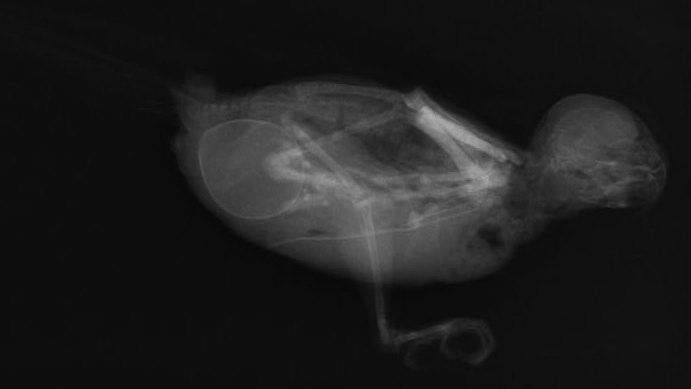

セキセイインコの卵詰まり 卵巣ホルモンの影響で大腿骨などの骨の密度が落ちて脱灰しているのがわかる。

前日までなかった卵がほかの臓器を圧迫するため、早急に取り出す必要がある。